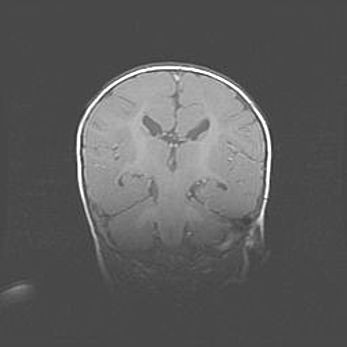

Множественные кисты обоих полушарий головного мозга, наибольшая из них в правой затылочной области. Ассиметричная атрофическая гидроцефалия.

Возраст: 7 месяцев

Вес: 5660 г

Пол: мужской

Окружность головы: 41,5 см

Срок гестации: 28-29 недель

Кисты головного мозга развиваются в результате многоочаговых некрозов вещества мозга и возникают вследствие перенесенной перинатальной инфекции, менингитов, энцефалитов, асфиксии, родовой травмы, расстройств мозгового кровообращения различного генеза. Образованию кист в веществе головного мозга плодов и новорожденных способствуют такие факторы, как высокое содержание в нем воды, недостаточная (или отсутствие) миелинизация и слабая астроглиальная реакция на повреждение.

Кисты могут сочетаться с гидроцефалией и другими поражениями головного мозга.